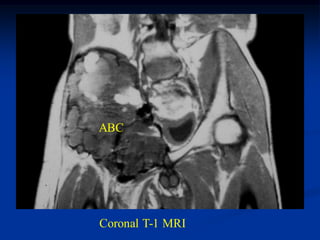

Case #997

25 year male with ABC pelvis

R

CT scan

ABC

CT scan lower level

CT scan thru pubic area

Coronal T-1 MRI

Axial T-2 MRI